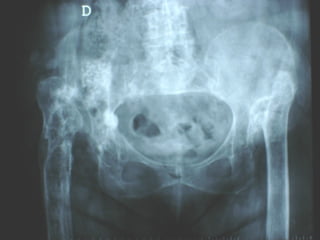

La lesione dell’apparato muscolo scheletrico che richiede  in ogni caso  un trattamento chirurgico con  priorità   assoluta  è la rottura dell’anello pelvico , che comporta una emorragia severa nel retro peritoneo e nella cavità peritoneale.

Immediata riduzione e fissazione del bacino

Se la risposta emodinamica a questo trattamento è buona il paziente verrà monitorato e potrà essere programmato un successivo intervento di osteosintesi definitiva

Angiografia e/o packing pelvico Se il paziente rimane instabile